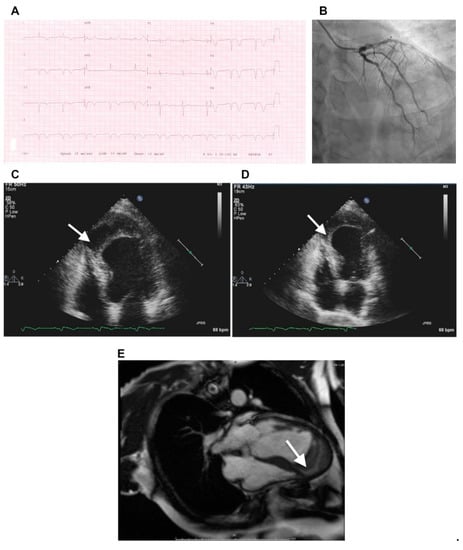

Figure 3.

(A) Electrocardiogram at presentation shows biphasic T wave in lead V3, deep T-wave inversion in leads V4, V5, and V6, and Q waves with T-wave inversion in the inferior leads, consistent with angiographic findings. (B) Coronary angiogram shows moderate stenosis at the proximal segment of the left anterior descending coronary artery, severe stenosis at midsegment, and complete total occlusion in the distal segment. (C–E) Transthoracic two-dimensional echocardiographic and cardiac magnetic resonance views of IDH. (C,D) At presentation, apical four-chamber view showing dissecting echo-free cavity (arrow). (E) An IDH was confirmed by gadolinium-enhanced magnetic resonance imaging, revealing a large thrombus (arrow) within the apical intramyocardial dissection cavity containing the hematoma in the apical segment. Roslan A, et al. CASE (Phila). 2017 August; 1(4): 159–162 [69].